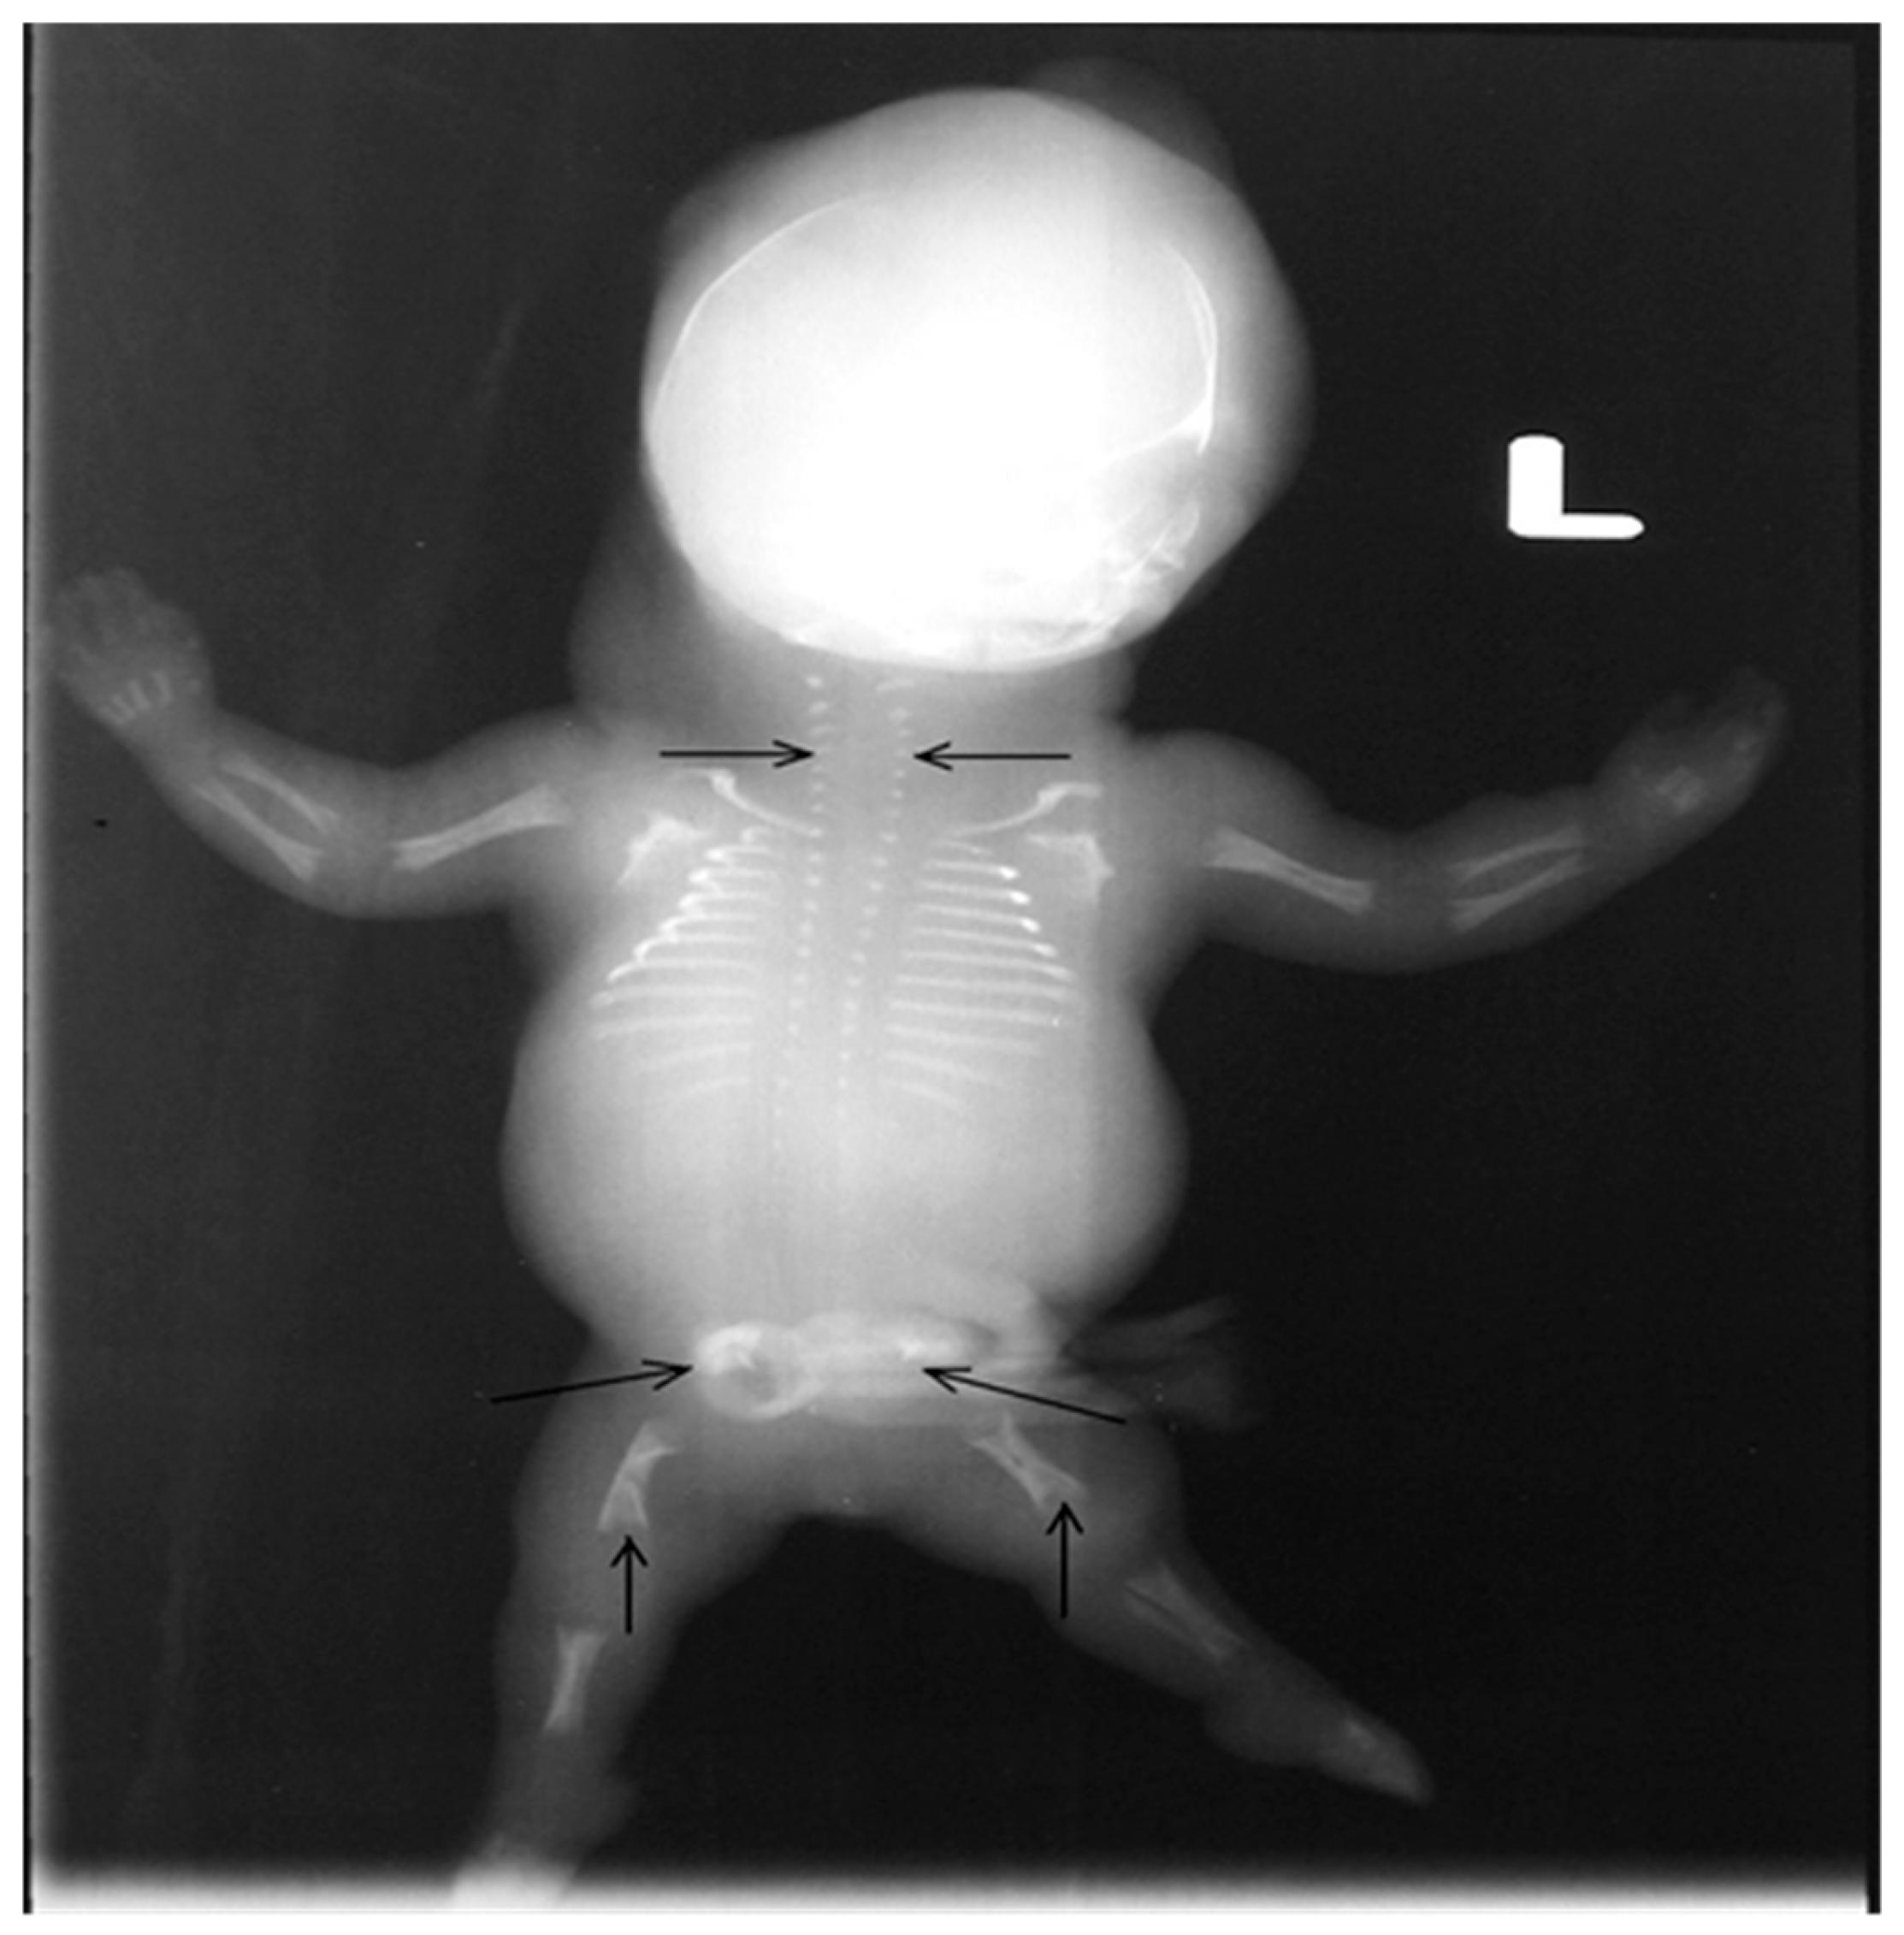

2. Case Presentation